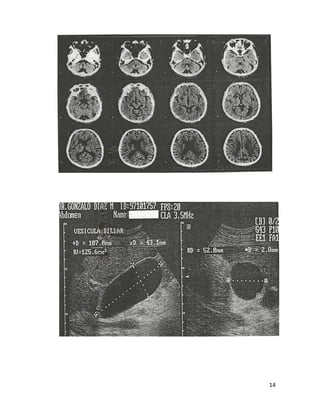

Estudios De Gabinete

Radiología

Ultrasonido

Tomografía